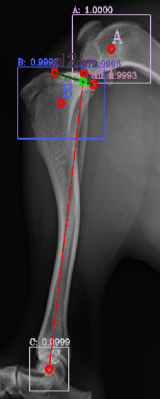

Following the identification of points of interests, and drawing of the lines of interest, i.e. the Functional Tibial Line (FTL) and the Medial Tibial Plateau Line (MTPL), another line is drawn such that the relation of new line and the FTL is 90°. Tibial plateau angle is the angle between this new line and the MTPL; this is shown in Fig. 3.

Most of the source dataset of over a thousand unique knee radiographs were distorted, had poor patient positioning, or were otherwise unfit for annotating. 250 of the original images were of sufficient quality to contribute to this effort. These images were set to have 6 different classes for training purposes, as mentioned and shown in Fig. 4. These were then trained using YOLOv3 [10] and the results of the predicted annotations are shown in Table I. From these predictions the centroids were extracted, which is then used to plot the FTL and MTPL. Then using the method mentioned in Section II, TPA is calculated. Examples of images, the region of interests detection and their respective TPA determination is shown in Fig. 6 and Table I: